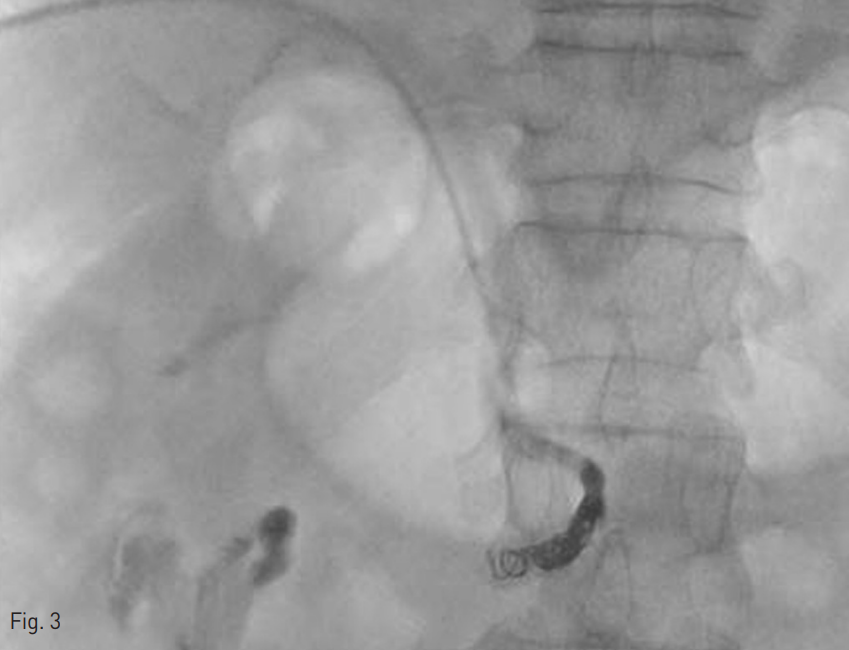

Fig. 3

After embolization for inferior feeding vessel, variceal blood flow was no longer visible

이에 N-buty1-2-cyanoacrylate (Histoacryl; B. Braun, Tuttlingen, Germany)와 Lipiodol(Guerbet, Paris, France) 1:2 혼합물을 이용하여 색전술을 시행하였고, 이 과정 중 색전물질 일부가 문맥전신단락을 통해 유출되는 것이 확인되었다. 그러나 이후 추적 조영술에서 문맥전신단락을 통한 조영제 유출은 확인되지 않아 PVA particle (Contour; Boston scientific, Natick, USA)를 통한 추가 색전술을 시행하였고 microcoils 5개 (Interlock and Tornado; Cook, Bloomington, USA)을 이용하여 영양혈관의 근위부에 색전술을 시행하였다 (Fig. 3).